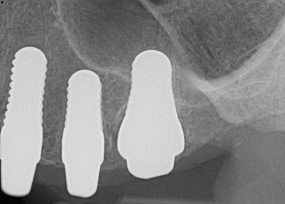

Fig 9. 12-week postoperative periapical radiograph.

Figure 9

Essentially, after integration and evaluation of soft tissue at 12 to 16 weeks subsequent to surgical placement of the ceramic implant, the implant is treated similarly to a natural tooth receiving a long-term restoration, and the protocol is the doctor's choice for soft-tissue management at the time of the final impression. Radiographic examination in Figure 8 and Figure 9 revealed that bone volume and soft tissue were preserved, primarily due to exceptional biocompatibility and the PRF biologics implemented after the atraumatic extractions.